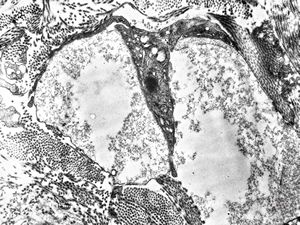

M, 3y. | cutaneous nerve